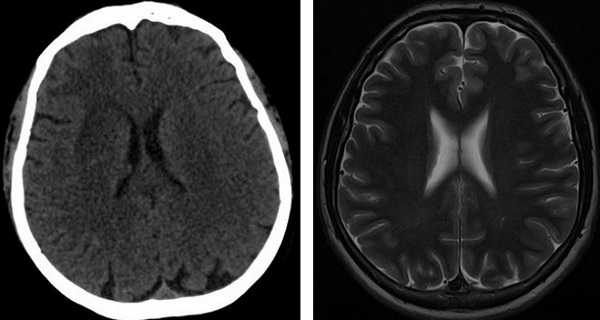

Оба диагностические исследования дают ценную информацию врачу. Содержимое головы изучают в виде серии снимков или трехмерного изображения. КТ основана на ионизирующем излучении (рентгеновском), поэтому ее не назначают беременным и маленьким детям. На снимках, полученных при компьютерной томографии, хорошо видны кости, отложения солей кальция на месте воспаления или опухоли, свежие очаги кровоизлияния (до 6 часов). В некоторых больницах нет магнитных томографов, назначают проведение КТ с контрастом. КТ станет методом выбора, если пациент имеет травмы черепа, симптоматику свежего геморрагического инсульта, при паразитарных кистах в мозге, очагах обызвествления.

КТ головного мозга МРТ головного мозга

В остальных случаях более информативной будет МРТ. Особенно ценная МРТ при болезнях мозжечка, стволовых структур мозга, при ишемическом инсульте, разрушении миелиновой оболочки нервов, психических болезнях. При отсутствии аппарата диагностику проводят теми методами, которые доступны, – УЗИ, рентген, КТ, ангиография, ЭЭГ, РЭГ.